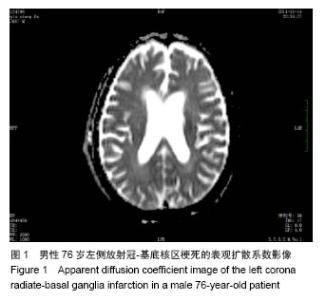

2.5 患者弥散张量成像参数与运动功能的相关性分析 脑梗死患者内囊后肢弥散张量成像参数与神经功能损伤 (NIHSS)无相关性(表4)。脑梗死患侧内囊后肢的表观扩散系数值和表观扩散系数指数与下肢Fugl-Meyer评分的总分负相关(分别为r=-0.457,P=0.049和r=-0.464,P=0.045,表5,图2A,B),而与改良Ashworth评分、Brunel平衡、步行速度、上肢Fugl-Meyer评分无相关性(P > 0.05)。患侧内囊后肢的表观扩散系数值和表观扩散系数指数与下肢Fugl-Meyer评分中的下肢运动功能部分负相关(分别为r=-0.504,P=0.028和r=-0.492,P=0.033,表5,图2C,D),与下肢Fugl-Meyer评分的下肢协调能力与速度、下肢腱反射无相关性。健侧表观扩散系数值、健侧各向异性分数值、患侧各向异性分数值和各向异性分数指数与运动功能的各项参数均无相关性(P > 0.05)。"